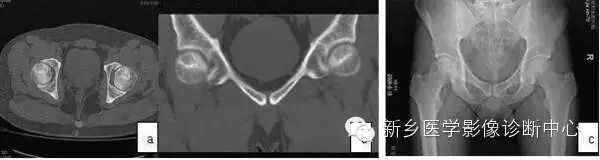

3.CT扫描对Ⅰ期ONFH的诊断作用有限,MRI出现阳性改变到CT扫描清楚显示病灶的间隔多数患者为6月~1年(4)。CT可清楚显示Ⅱ期ONFH病灶,典型的改变为硬化带包绕坏死灶,部分ONFH的坏死灶内显示斑点状或片状骨化(图2)。Ⅲ期ONFH的CT扫描可显示股骨头病灶皮质骨断裂(冠状位、矢状位、或轴位重建)。因此,CT扫描对清楚显示病灶范围、部位、修复情况及鉴别Ⅱ、Ⅲ期有重要作用。

图2 CT显示坏死灶明显,硬化带形成(a,b);X线片坏死灶显示不清(c)。